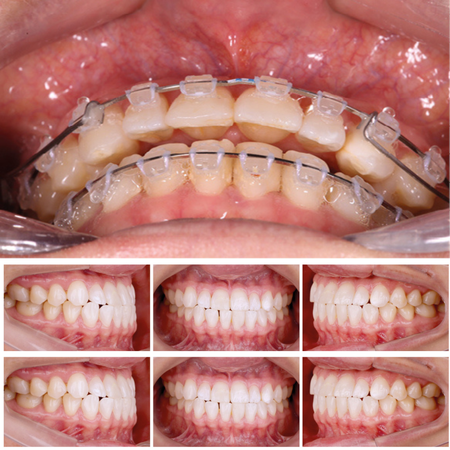

Optimizing clear aligner outcomes with auxiliary mechanics: case reports

INTRODUCTION: Clear aligner therapy is a widely used orthodontic approach; however, achieving certain movements, such as rotation and extrusion, remains challenging. These difficulties are particularly pronounced in rounded teeth, such a...

Tooth Movement Techniques Orthodontic extrusion Orthodontic appliances, removable

Optimización de los resultados del tratamiento con alineadores Ortodóncicos mediante mecánicas auxiliares: reporte de casos

INTRODUCCIÓN: La terapia con alineadores es un enfoque ortodóncico ampliamente utilizado. Sin embargo, la realización de ciertos movimientos, como la rotación y la extrusión, sigue siendo un desafío. Esta dificultad es particularme...

Aparatos ortodóncicos removibles Extrusión ortodóncica Alineadores ortodóncicos Movimiento dentario